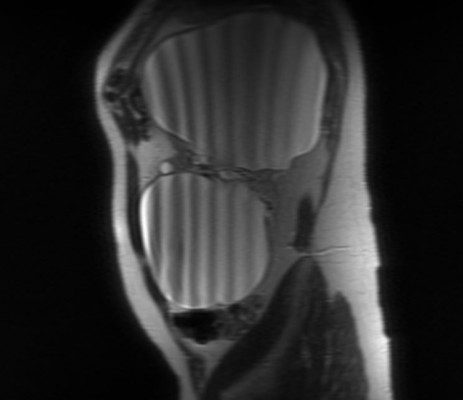

В орловской областной клинической больнице прооперировали пациента с гигантскими кистами почки. Их общий объём составил около 4 литров.

Обе кисты находились на одной почке . Сам орган занимал всю левую часть брюшной полости до малого таза.